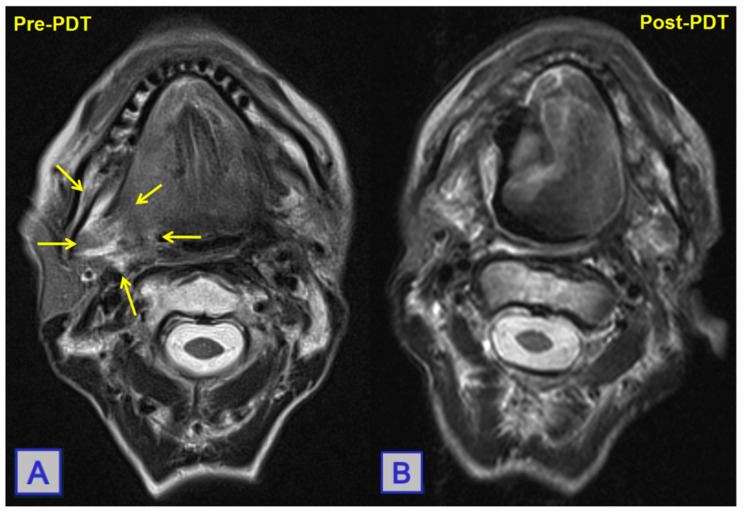

The value of PDT in palliation was investigated in a study conducted by Jerjes et al. A total of 21 patients were included in the study, all of whom had been referred for the treatment of recurrent or advanced tongue base cancers, with a mean follow-up of 36 months reported (Figure 11, Figure 12 and Figure 13). Of these patients, two-thirds had not been offered further conventional treatment, and an multi-disciplinary team (MDT) decision was made to offer mTHPC interstitial-PDT (iPDT) under ultrasound guidance. Although survival was measured (eight patients died), the study focused on QoL improvements, and demonstrated improvements in speech and swallowing in over half of the patient group. Over half of the patient group were deemed to be showing a “good response” to treatment, and two patients were found to have a reduction in lesion size. The study concluded that in the group of patients studied, significant improvements were seen, pointing towards the promise of further iPDT use in palliative care [42].

Figure 11.

MRI showing a posterolateral tongue-base squamous cell carcinoma. Pre-PDT (A), a large mass is seen. Post-PDT (B), a reduction in lesion size with widespread tumour necrosis is noted. Reprinted with permission from ref. [10]. Copyright 2010 Clin. Oncol. (R. Coll. Radiol.).